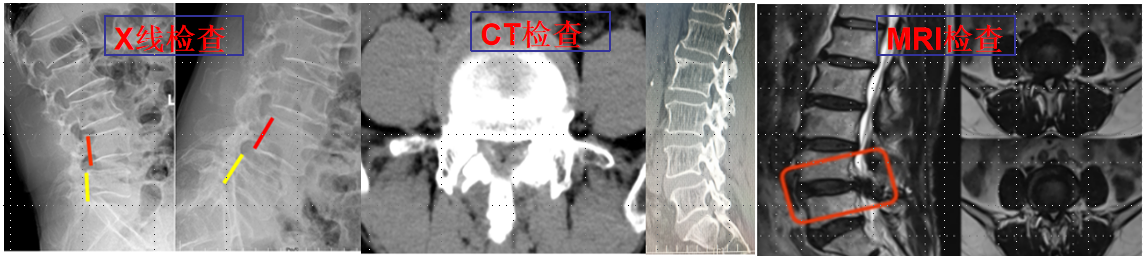

椎间孔镜技术:

利用椎间孔镜从患者腰椎侧方或者后方进入达到椎间盘突出或者其他病变部位,用专用工具将突出(脱出)的椎间盘组织或病变取出(去除)从而达到治疗椎间盘突出或者椎管狭窄的目的。它的优势在于:局部麻醉、微创、切口小(仅约7mm)出血少,恢复快(第二天即可佩戴硬腰围下地)及疗效好。

539650c2baae42ea976bd4bf6a4f7947.Png